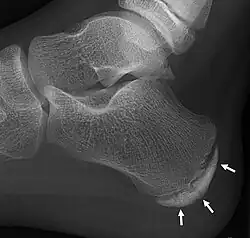

| X-ray of the foot of an 11-year-old child, showing sclerosis and fragmentation of the calcaneal apophysis. This is a sign of low sensitivity and specificity of Sever's disease, because those with Sever's disease may not have it, and this appearance is also present in feet without pain.[1] | |